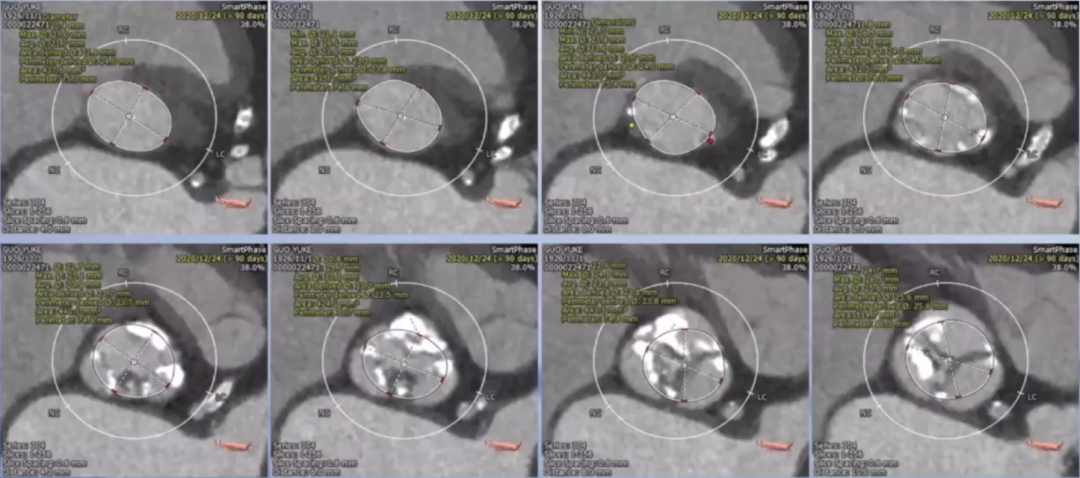

患者为94高龄老年男性患者,5年前出现胸闷憋喘,活动后明显,诊断为主动脉瓣钙化并重度狭窄,1年前症状加重,药物治疗好转后半年前再次加重。术前超声检查结果显示,主动脉瓣平均跨瓣压差63 mmHg;峰值流速5.02 m/s,左室射血分数29%,心功能极差,诊断为主动脉瓣钙化、重度狭窄并轻、中度反流。且患者合并有心力衰竭、冠脉支架病史、高血压三级、右侧髂总动脉闭塞等。术前CT结果显示,瓣环平均直径24 mm,左室流出道直径24 mm,主动脉瓣窦部内径约30 mm左右,STJ为30 mm左右,左、无冠窦存在钙化融合迹象,左冠开口高度14.1 mm,右冠开口高度11.8 mm。

瓣下平均直径约为24 mm,瓣上平均直径也约为24 mm,瓣上6 mm及8 mm处为可能的锚定点。综合患者实际情况及瓣膜特点,计划选择TaurusElite 23 mm可回收瓣膜。

在瓣膜型号的选择方面,根据术前CT结果可以发现,患者瓣环直径与左室流出道直径均在24 mm左右,但瓣环平面上方4 mm处就开始出现瓣叶融合的情况,左无之间、左右之间都存在未能完全打开的瓣叶,这些瓣叶是否能打开,影响了最终瓣膜型号的选择。但从融合处的钙化情况来分析,瓣叶打开的可能性不大,当不能打开瓣叶时,主动脉瓣下方直径24 mm,上方直径约22 mm,因此选择23 mm瓣膜是合理的。同时,考虑到今天使用的瓣膜为TaurusElite可回收瓣膜,其23#瓣膜的底边直径为24.5 mm,完全可以贴合瓣膜,避免反流的发生,这也是今天手术中,虽然瓣膜有所下移,但依然没有严重反流并发症发生的原因。